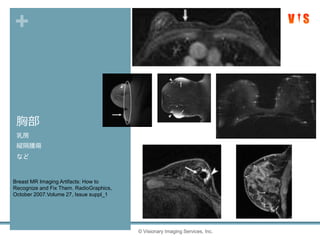

胸部

乳房

縦隔腫瘍

など

© Visionary Imaging Services, Inc.

Breast MR Imaging Artifacts: How to

Recognize and Fix Them. RadioGraphics,

October 2007.Volume 27, Issue suppl_1